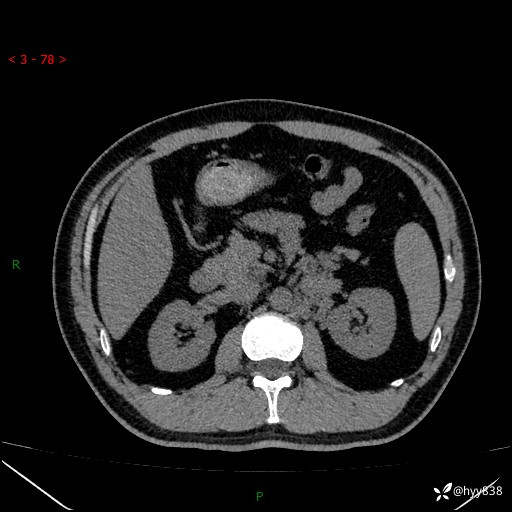

现病史:患者3月余前检查发现左侧腹膜后占位,大小约3.7*4.9cm,平素无腰疼,无肉眼血尿,无尿频尿急等不适,当时未特殊处理,在门诊复查CT提示左侧腹膜后占位,门诊拟“左侧腹膜后占位”收入院。 起病以来,患者精神佳,饮食、睡眠良好,大小便正常,体力体重无明显变化。

腹膜后CT平扫+增强